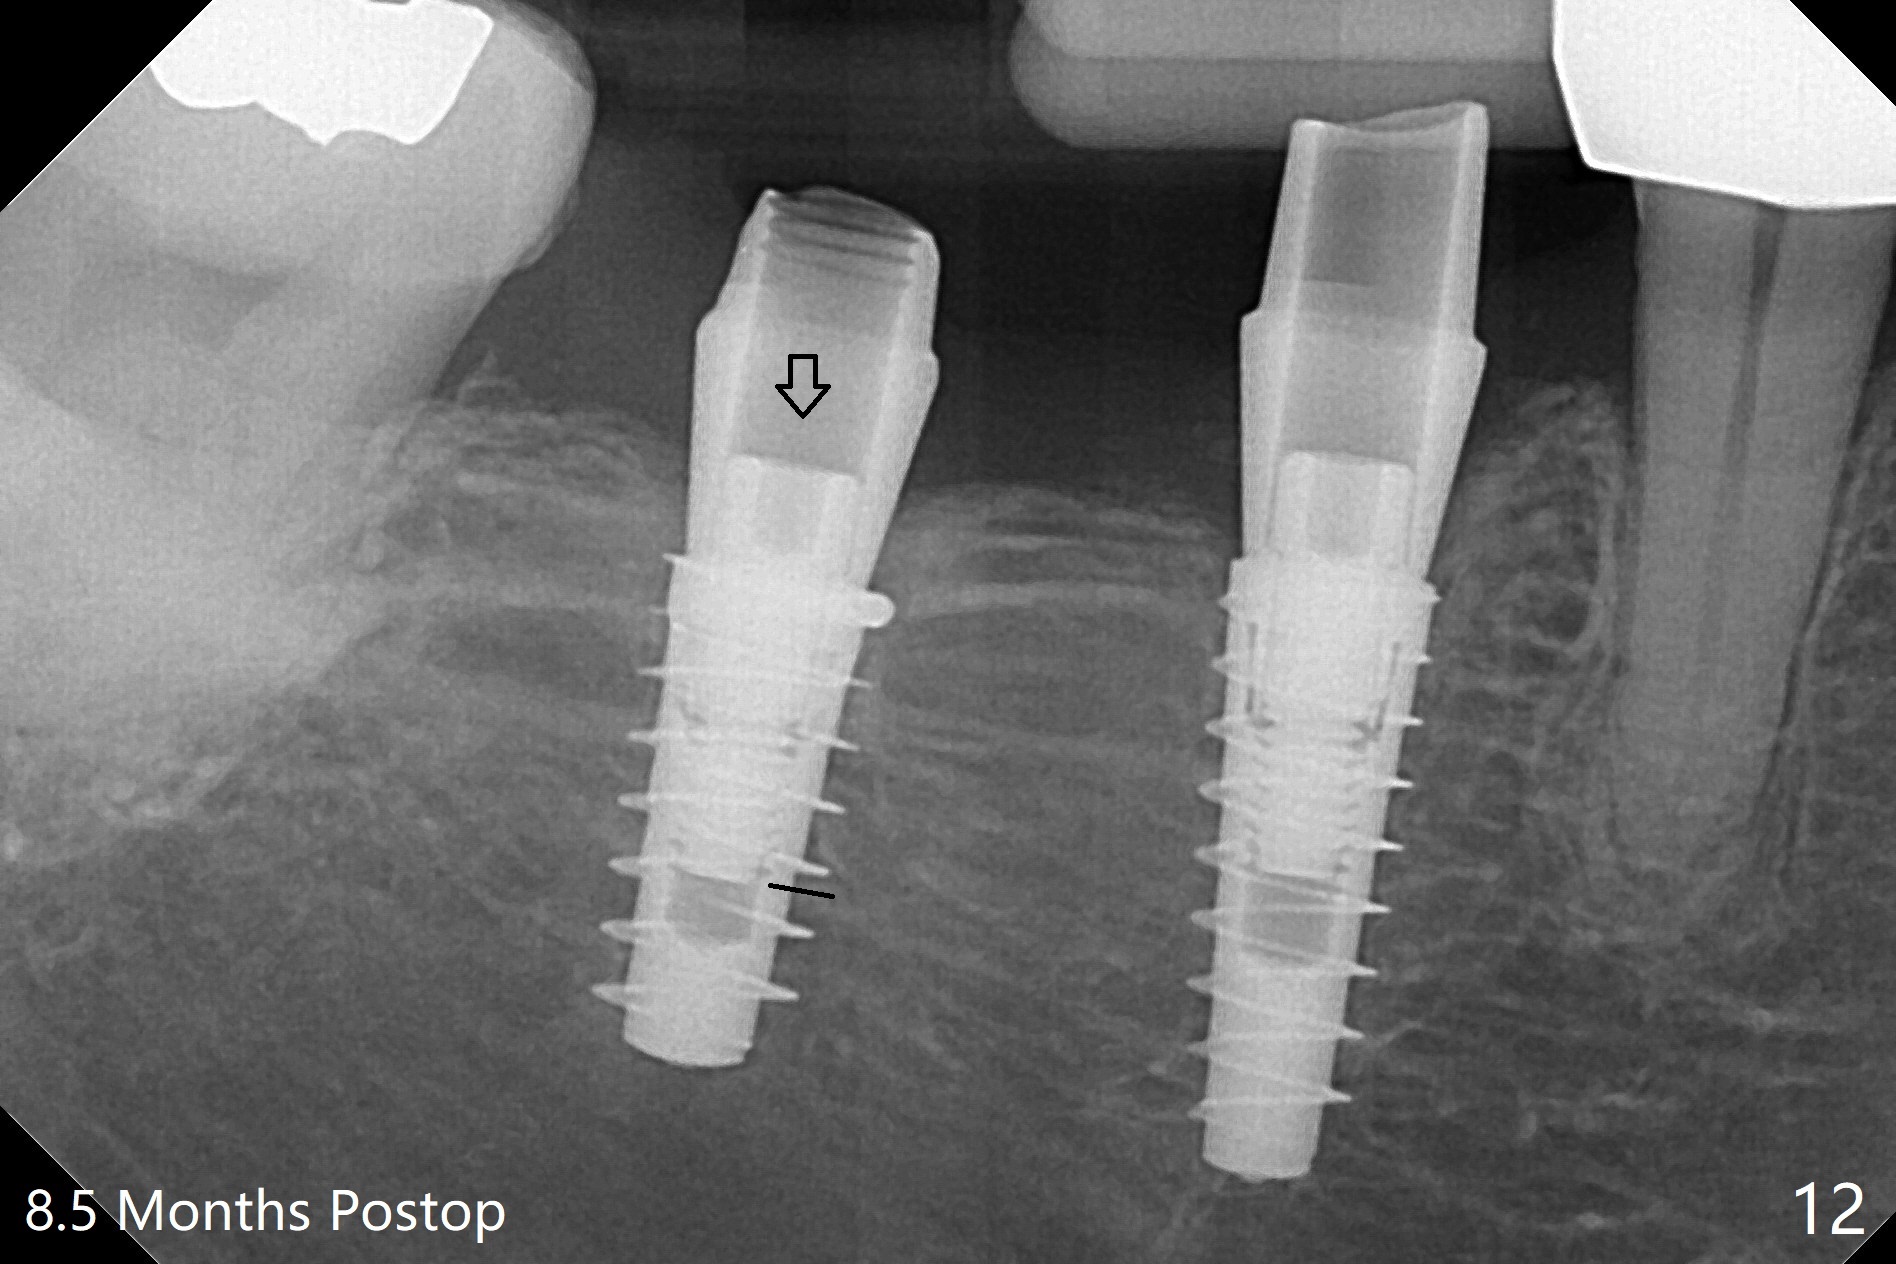

害怕病人局麻药很慢起效,术中身体会动,术中决定减小右下6,7植体直径0.5毫米(与导板设计相比),一旦植体越过牙槽嵴顶骨皮质,稳定性突然减低(图一)。尽管扭力10-15Ncm,为了避免二期手术,放置愈合基台(图二),6基台没有就位(箭头),因为植体种太深了,牙槽骨阻挡(*)基台就位。当取出6基台时,植体一起旋出,重新植入时,就没有种那么深(图三:箭头,与图一,二对比)。由于扭力低,只好放置愈合帽,骨粉(*),GEM Cap(6-9月胶原膜)和牙周胶水。由于导板设计缘故,左上5拔除,种植后,才开始左上3一段式植体植入(图四),5也植入太深(图五),必须放置最小直径最长袖(cuff)的基台(图六),今后导板即刻植牙先不要到达设计深度。术后一周CT显示尖牙植体位于牙槽骨内(图七 (>:腭侧牙槽嵴))。Bone graft fills in the buccal apical defect at #13 one week postop (Fig.8 <). 术后两个月左上3临时牙冠折裂,5松动(图九,十),后者取出衬里,软组织愈合。术后8个月左上3,5取模,右下6 uncover,愈合帽表面覆盖骨质,把7号牙愈合基台放到6号牙上,而7号牙放置4.5x4(4)毫米修复基台,固定牙周敷料,这样6号牙伤口不必缝合。术后8.5个月右下6放置4.5x7.5(4)毫米基台,发现7基台没有就位(图十一:箭头),通过旋转7 基台,终于就位(图十二),螺丝往下移位(与图十一:横线对比),但是基台边缘太低,不利于取模。改用5.5x4(5)毫米UF基台,临床上不能就位,局麻使用5.5毫米Profile Drill后,才能就位(图十三),螺丝下端超越最低螺沟(横线)。